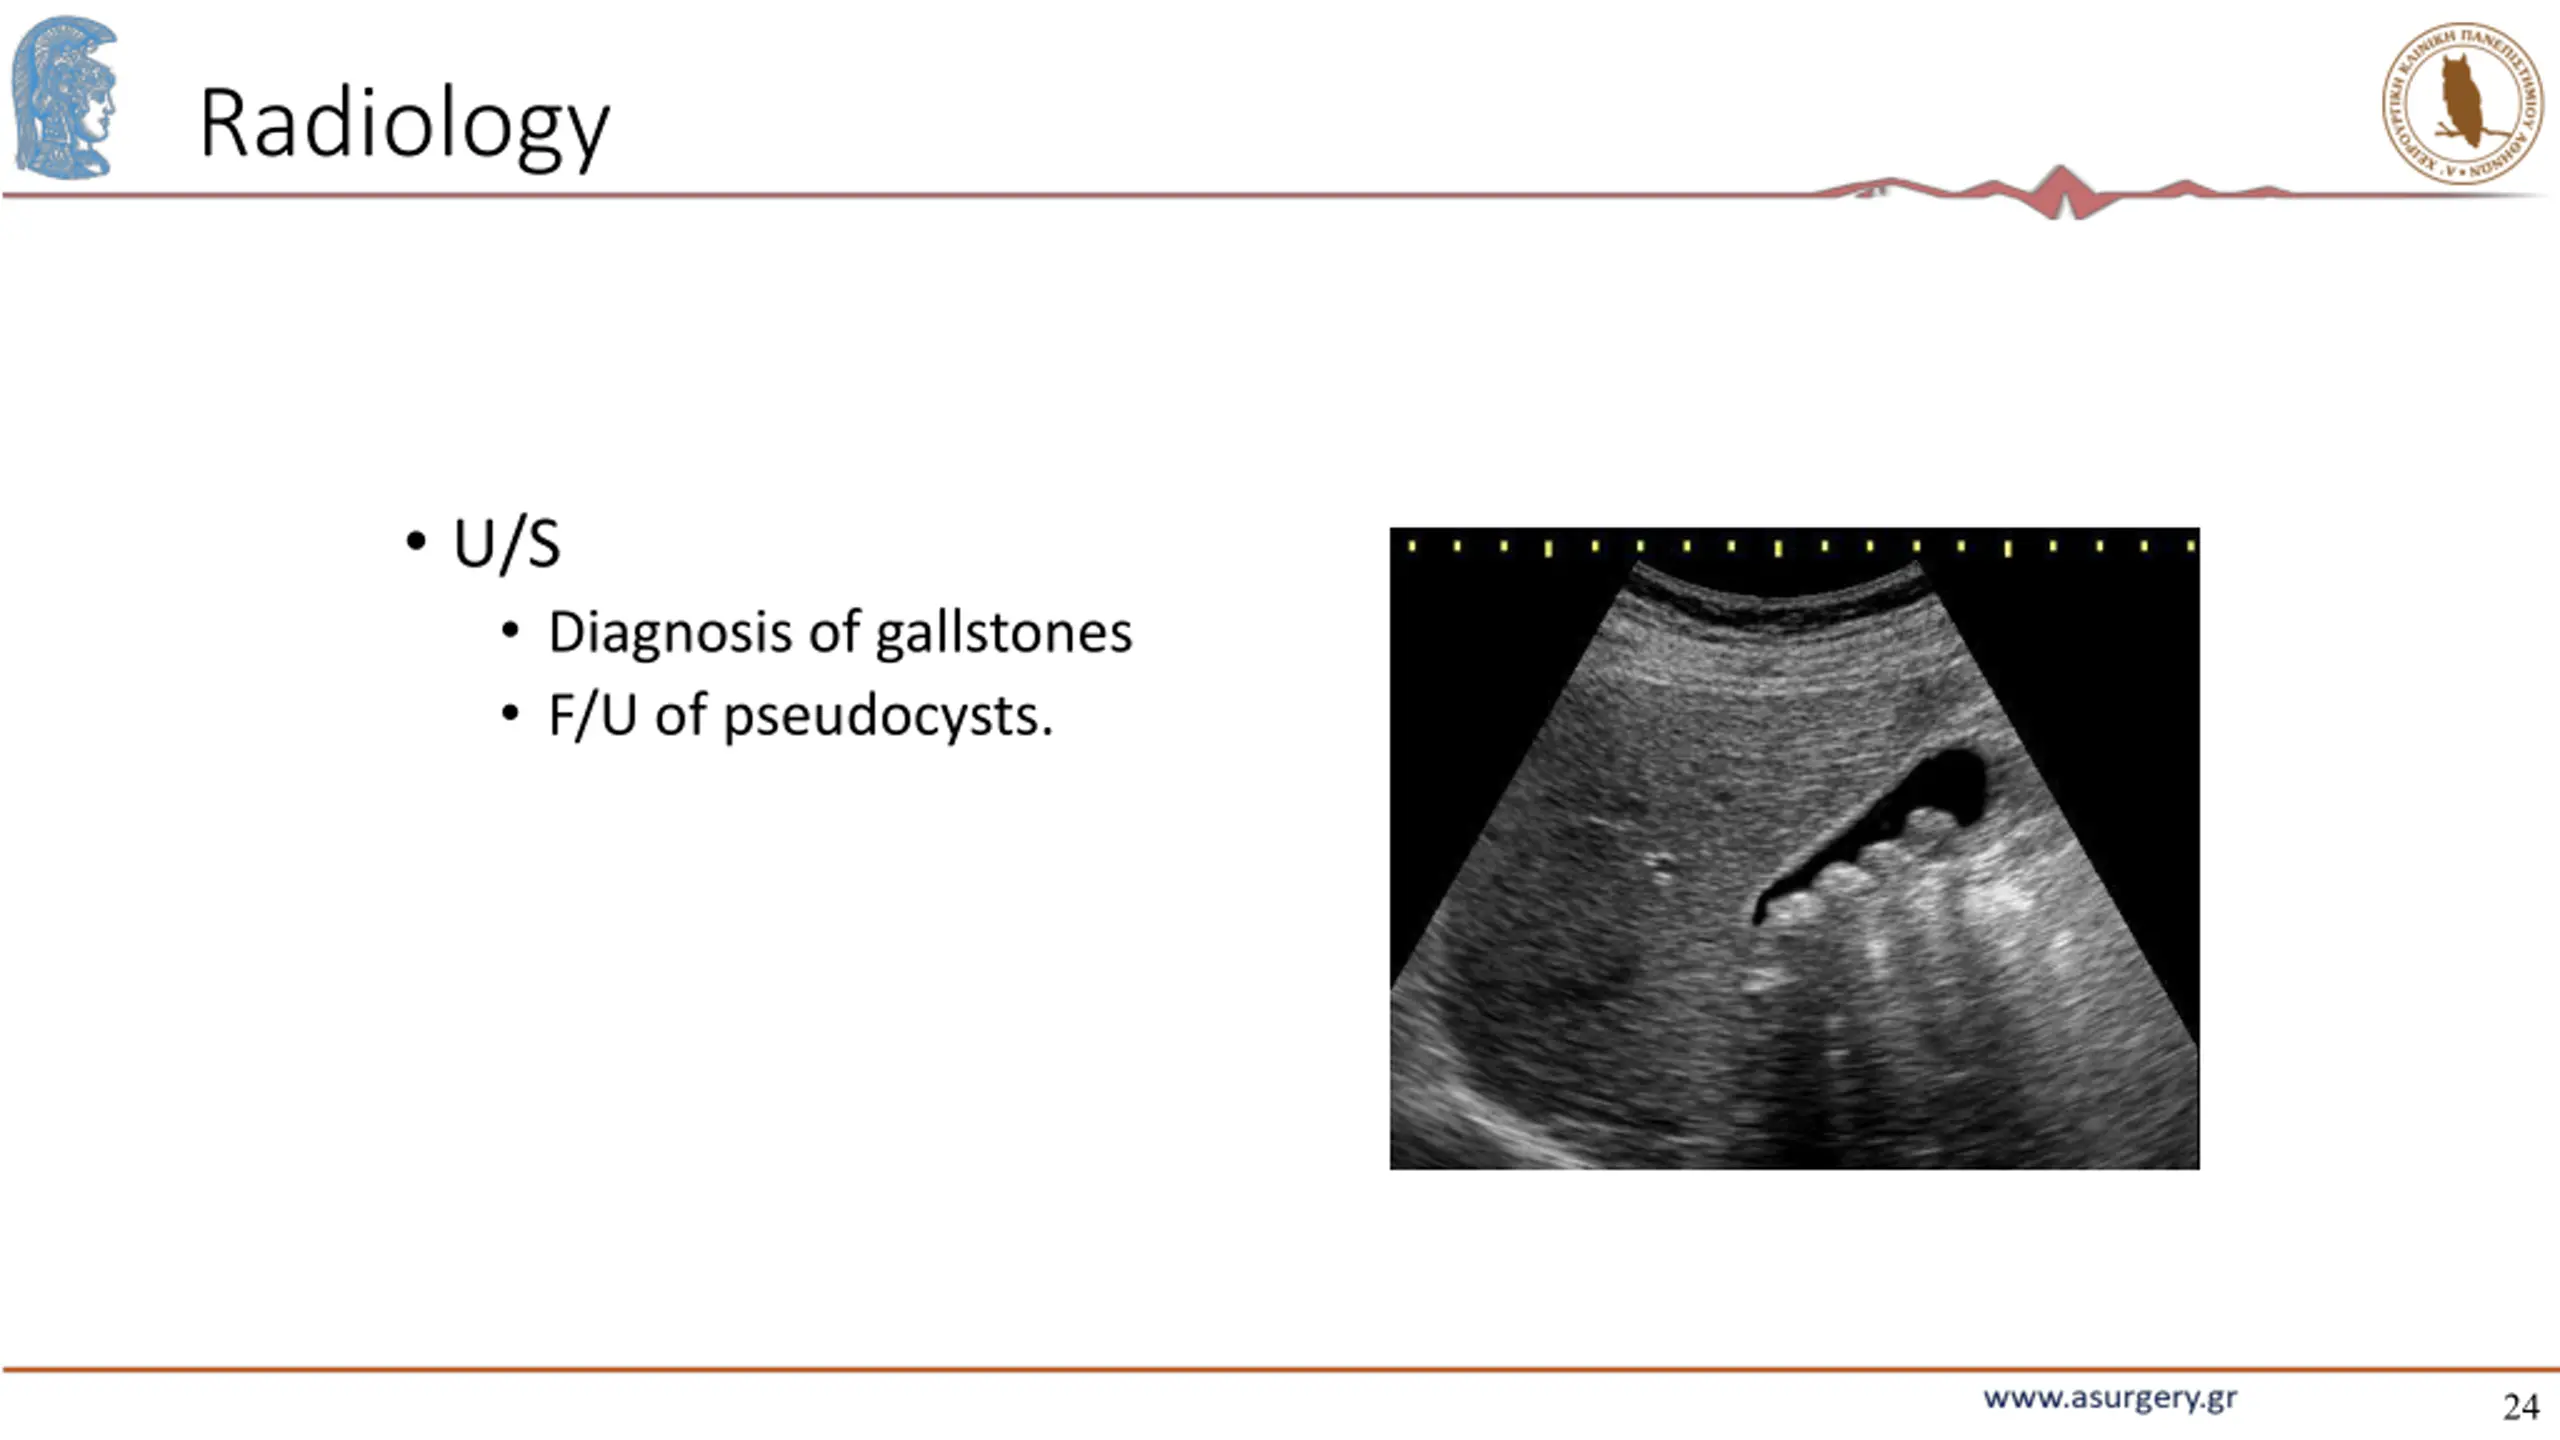

24. Radiology U/S Diagnosis of gallstones F/U of pseudocysts. 24